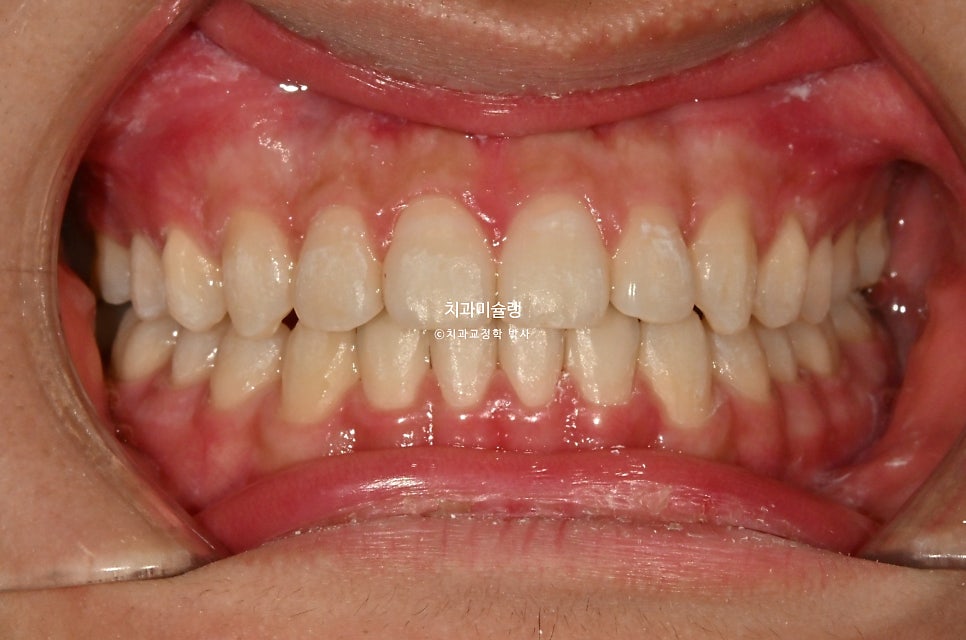

2026년 3월 – 치료 완료

중심선은 정확히 맞으며

어금니 교합관계는 좌우 모두 1급을 달성

치료 전후 비교 결과

이제 전후 비교 보겠습니다.

간단한 교정이 아니고서야 미진한 부분 전혀 없이, 즉 재제작 없이 치료를 마무리하기 힘든데 해외에서 가끔 내원하면서도 장치를 열심히 껴준 덕에

쉽지 않는 난이도의 치료를 재제작 없이 마무리 했습니다.

교합관계는 3급에서 1급으로 개선되었죠.